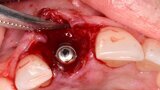

Figura 7. Implante de conexión interna insertado 2 mm por debajo de la cresta ósea, independientemente del defecto existente y a 55 Nw. Al no existir margen vestibular, tomamos como referencia los dos picos óseos de las papilas y entre ellos trazamos una línea imaginaria que los una enterrando el hombro unos 2 ó 3 mm por debajo de ella.